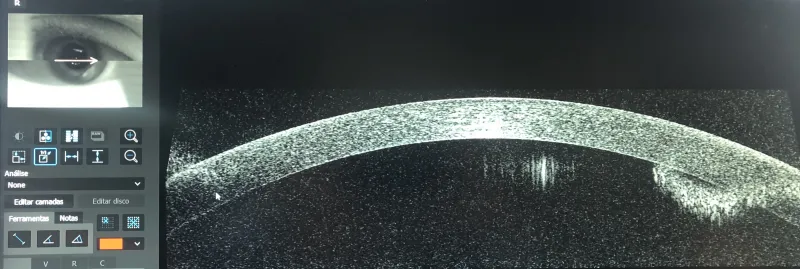

Paquimetria ocular é um exame oftalmológico fundamental para avaliar a espessura da córnea, sendo uma ferramenta essencial para diagnósticos precisos e tratamentos eficazes.

Realizada através da paquimetria ultrassônica, essa avaliação é crucial para identificar condições como ceratocone, glaucoma e outras doenças que afetam a espessura corneana.